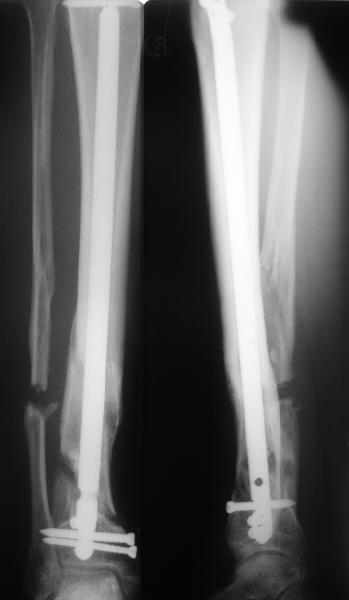

Думаю наиболее оптимальным вариантом будет реостеосинтез стержнем.

Учитывая сроки, вполне вероятно, что одномоментно устранить смещение не получится, поэтому может потребоваться 2-х этапное лечение: 1)Удаление гвоздя и ЧКО 2) ЗИО с рассверливанием после восстановления оси и длины.

Гвоздь, конечно же, лучше брать с расширенными возможностями дистального блокирования. Линейка таких гвоздей сейчас представлена довольно широко различными фирмами. У нас в клинике наиболее часто

используется гвоздь MetaDiaFix-T, выпускаемый предприятием ЦИТО. В гвозде дистально раполагается овальное отверстие, в которое очень удачно вводятся два винта и заклиниваются между собой, обеспечивая угловую стабильность. Пример использования такого гвоздя привожу ниже.